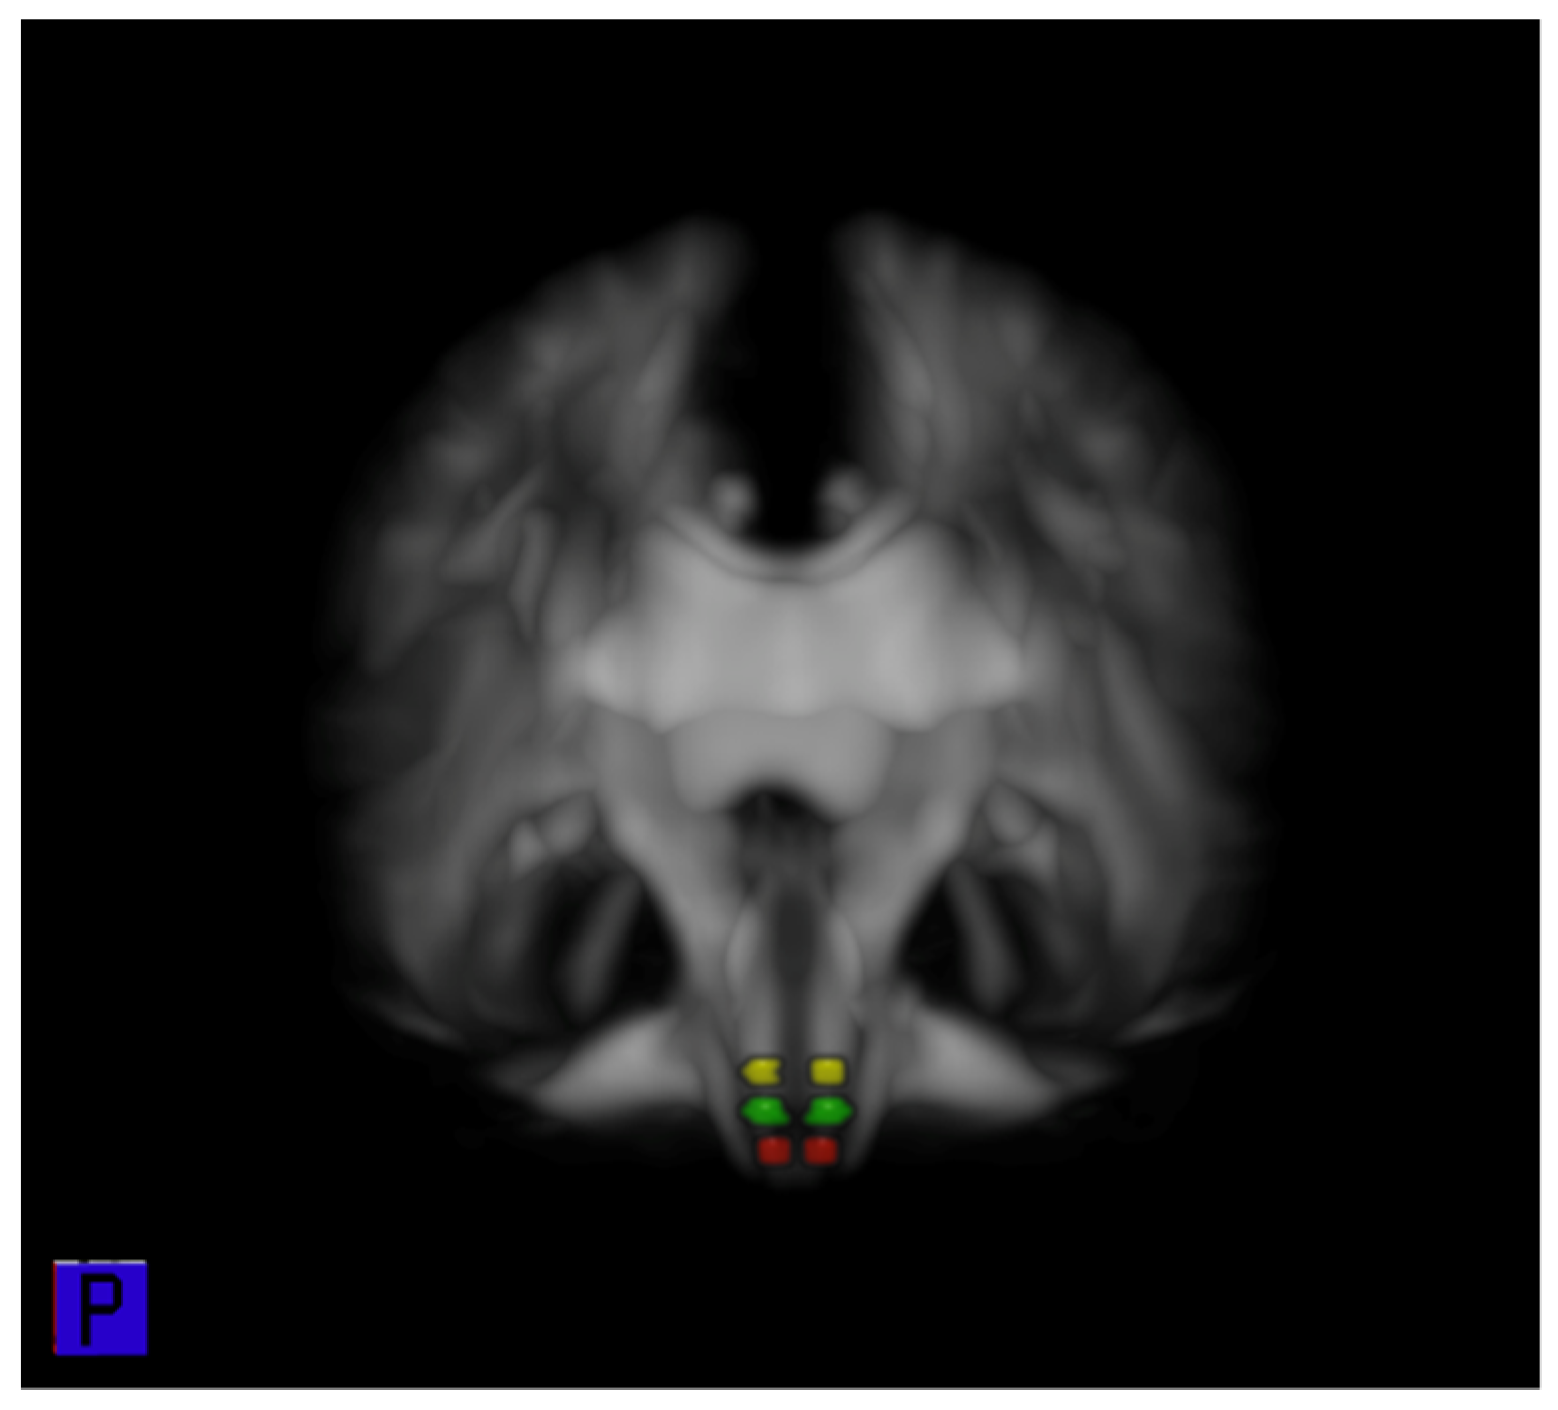

3.4. ROI Analysis of FA of the CRP in the Brain Stem

3.5. ROI Analysis of FA of the CRP in the Pons, Pontomedullary Junction, and Medulla